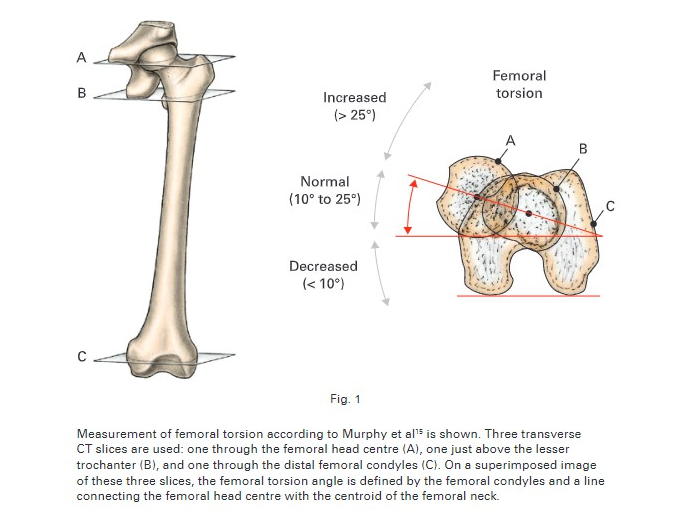

Methode Murphy

Torsion fémorale

A + B + C (tetefem + colfem + condyles)

A + B + C (tetefem + colfem + condyles)

Coupes

A

Tête fémorale

B

Col fémoral

Col fémoral

C

Condyles (Arche romaine)